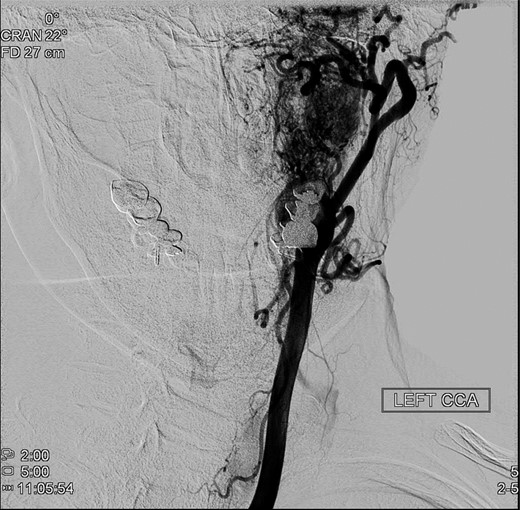

An operative approach was selected in the setting of progressive neurologic deficits with increasing tumor size. The patient underwent left internal carotid artery angiography (Fig. 6); vascularity of the PGL is demonstrated. The patient underwent left transjugular craniotomy with temporal bone resection, extensive resection of the left PGL, left carotid resection, cranial nerve IX, X, XI and XII resection, with anatomic preservation of the cochlea and facial nerve. In addition, intraoperative stereotaxis treatment was elected to reduce risk of disease recurrence. Postoperative CT imaging (Fig. 7) showed operative changes from the left temporal craniotomy and resection. Pathology confirmed the diagnosis of malignant PGL with positive margins.

Preoperative angiography shows intricate vascularity of the PGL.